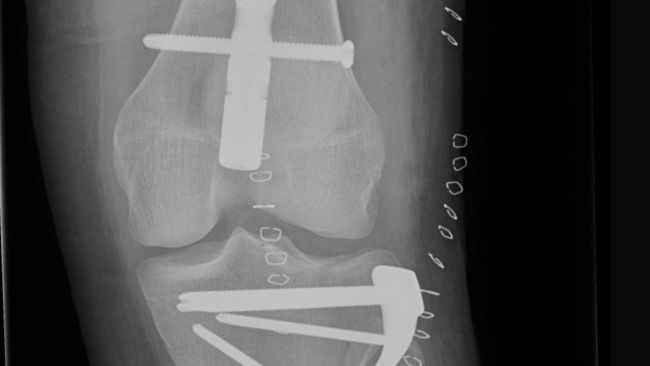

сломана левая нога и повреждены мышцы колена,

разорваны связки правой ноги и